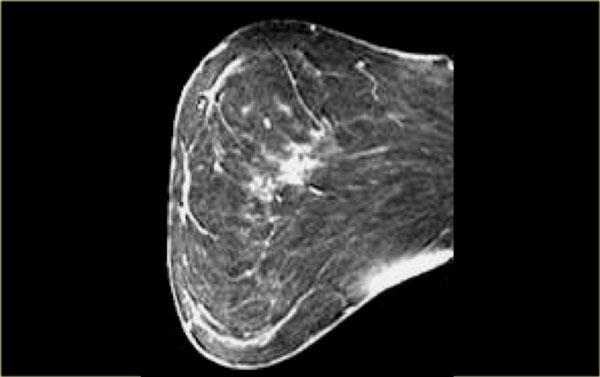

Bên trái, hình ảnh cho thấy một khối có hình dạng bất quy tắc với các tua gai và kiểu ngấm thuốc bên trong không đồng nhất, được xác định là ung thư biểu mô tiểu thùy xâm nhập.